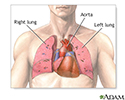

Heart-lung transplant - series - Normal anatomy

Presentation